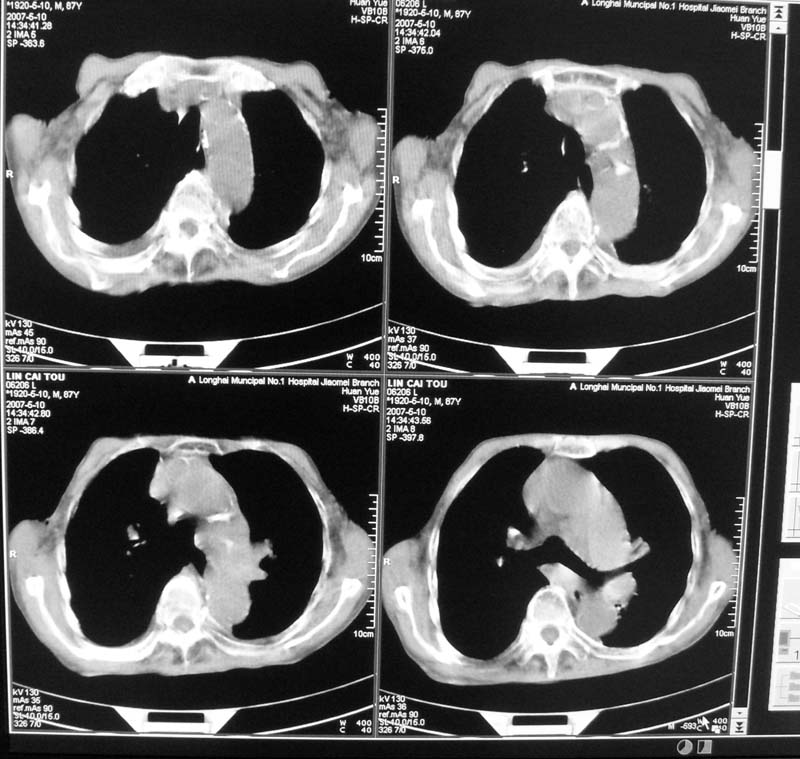

以下是引用小初学者在2007-5-12 16:26:00的发言:[br]1、心衰肺水肿两侧胸腔积液2、心包积液3、心瓣膜钙化